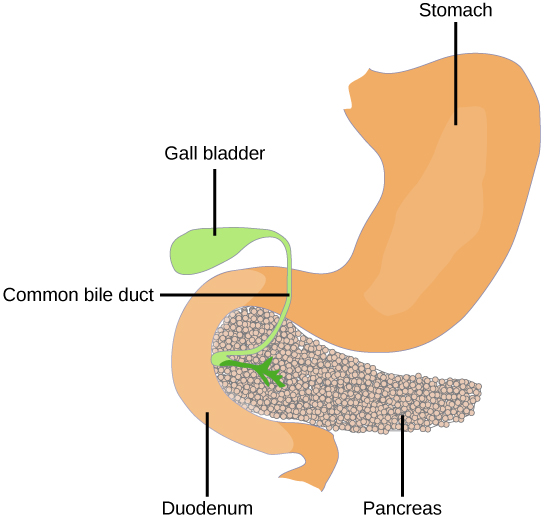

Pancreas

The pancreas, illustrated in Figure, is an elongated organ that is located between the stomach and the proximal portion of the small intestine. It contains both exocrine cells that excrete digestive enzymes and endocrine cells that release hormones. It is sometimes referred to as a heterocrine gland because it has both endocrine and exocrine functions.

The endocrine cells of the pancreas form clusters called pancreatic islets or the islets of Langerhans, as visible in the micrograph shown in Figure. The pancreatic islets contain two primary cell types: alpha cells, which produce the hormone glucagon, and beta cells, which produce the hormone insulin. These hormones regulate blood glucose levels. As blood glucose levels decline, alpha cells release glucagon to raise the blood glucose levels by increasing rates of glycogen breakdown and glucose release by the liver. When blood glucose levels rise, such as after a meal, beta cells release insulin to lower blood glucose levels by increasing the rate of glucose uptake in most body cells, and by increasing glycogen synthesis in skeletal muscles and the liver. Together, glucagon and insulin regulate blood glucose levels.

The pancreas lies in the abdomen between the stomach and the small intestine. Clusters of endocrine cells in the pancreas form the islets of Langerhans, which are composed of alpha cells that release glucagon and beta cells that release insulin.